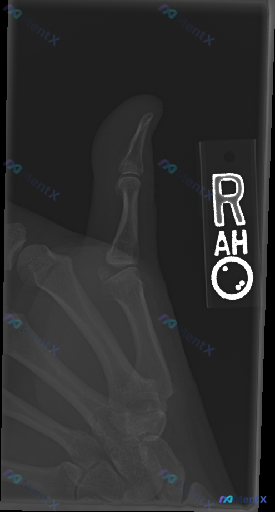

- 检查部位:右侧大拇指X光(侧位/斜位)

- 影像表现:远节、近节指骨及第一掌骨皮质连续,骨小梁清晰,关节对位良好,软组织也没看到明显肿胀或异物

- 影像结论:未见明确骨折、脱位或显著退行性病变

但这份资料的背景是「临床怀疑存在异常」——也就是说患者应该有疼痛、活动受限之类的症状。